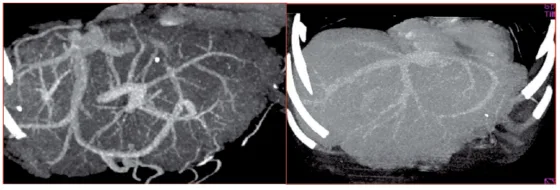

L’échographie-Doppler a une sensibilité diagnostique de plus de 75 %. C’est probablement l’examen le plus spécifique pour le diagnostic de SCB, dès lors que le radiologue a été informé de cette suspicion diagnostique. L’IRM et le TDM permettent de confirmer ce diagnostic. Les signes spécifiques sont : un matériel hypoéchogène remplissant une veine élargie, une sténose avec une dilatation en amont, un cordon hyperéchogène remplaçant l’une des principales veines hépatiques, des voies de dérivations collatérales intrahépatiques. La concordance entre ces anomalies échographiques et les données de la nécropsie ou de la veinographie sont excellentes, excepté lorsque l’occlusion est limitée à un ostium d’une veine hépatique et peut donner un aspect faussement normal de cette veine ; l’échographie-Doppler pulsé et couleur montre alors, au site de la sténose, une augmentation importante des vitesses circulatoires et, en amont de la sténose, une démodulation du flux remplaçant la morphologie triphasique habituelle. Des veines hépatiques non visibles, tortueuses ou de calibre réduit sont des données fréquentes ; comme ces anomalies sont également observées en cas de cirrhose sans obstruction des veines hépatiques, elles ne peuvent être utilisées comme argument diagnostique. L’échographie permet habituellement de reconnaître l’invasion tumorale intraluminale et la compression des veines hépatiques.

La tomodensitométrie doit être utilisée avec précaution en cas d’insuffisance rénale ou d’ascite réfractaire. Les signes indirects comme le remaniement de la forme du foie, l’ascite, et une parenchymographie hétérogène après injection de produit de contraste orientent vers le diagnostic. La mise en évidence de l’obstruction des veines hépatiques est quelquefois difficile et il peut exister des faux-positifs, notamment en cas de cirrhose ancienne. La tomodensitométrie est utile pour caractériser la circulation collatérale inter sushépatique, la veine cave inférieure, le tronc porte, les nodules et rechercher des arguments pour un SBC secondaire aux tumeurs du foie ou du rétropéritoine.

Les grosses veines hépatiques sont bien étudiées par l’IRM. Cette technique semble aussi performante que l’échographie pour mettre en évidence l’obstruction des veines hépatiques et la circulation collatérale inter sushépatique. Elle pourrait être supérieure à l’échographie pour étudier la veine cave inférieure. La thrombose vasculaire donne un signal élevé dans les séquences en écho de Spin et l’absence de signal en écho de gradient. Le parenchyme hépatique est habituellement le siège d’un hypersignal lors des séquences pondérées en T2 à la phase aiguë, et d’un hyposignal en T2 à la phase chronique, peut-être en raison de la fibrose.